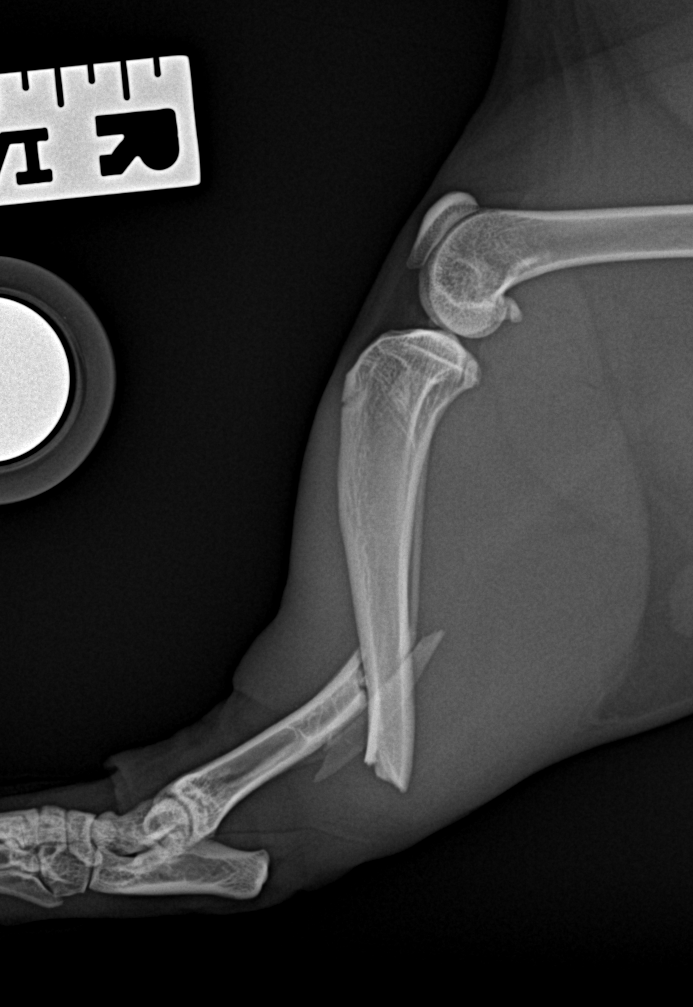

最小侵襲整形外科 脛骨を骨折した猫が足を痛がっているので手術して欲しいと主治医から連絡がありました。外科用イメージを使って、髄内ピンとプレートによる固定術を行い、翌日退院しました。この手法は皮膚や筋肉を大きく切開しないというメリットがあります。 症例カテゴリー 放射線治療整形外科軟部組織外科脳神経外科内科腫瘍外科救急・集中治療リハビリテーション科腫瘍内科内視鏡科脳神経科呼吸器外科中医・漢方猫の腎移植循環器科